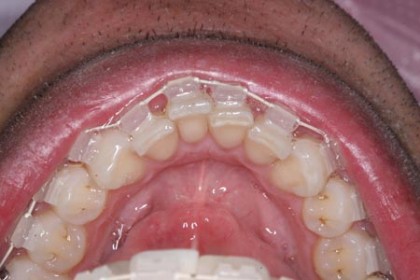

Trước và sau khi chỉnh nha bằng Six Month Smiles

Hệ thống niềng chỉnh răng “Six Month Smiles” là phương pháp thay thế đầy sáng tạo cho phương pháp niềng răng truyền thống. Đây là một bước cải tiến mới so với phương pháp chỉnh nha truyền thống nên kế thừa được tất cả các ưu điểm và khắc phục những nhược điểm của chỉnh nha truyền thống (Hệ thống chỉnh nha truyền thống bao gồm khung dây và mắc cài bằng kim loại, thời gian chỉnh nha khoảng từ 18 đến 24 tháng). Đây là phương pháp bảo tồn tối đa (tức là biện pháp ít xâm lấn nhất) để cải thiện nụ cười của bạn mà ít gây ra sự khó chịu và cảm giác e ngại trong giao tiếp khi mang mắc cài kim loại. Bệnh nhân nha khoa có thể có được kết quả tương tự niềng răng truyền thống, đặc biệt cho kết quả chỉ trong sáu tháng.

Với khung dây Chameleon có màu trùng với màu răng, làm cho khó bị phát hiện khi mang nó. Đi kèm với dây này là mắc cài Lucid Lok trong suốt (không màu), làm cho chúng gần như vô hình. Sử dụng phương pháp điều trị nha khoa này bệnh nhân có thể có hàm răng thẳng nhanh hơn nhiều so với những khí cụ truyền thống trước đây.